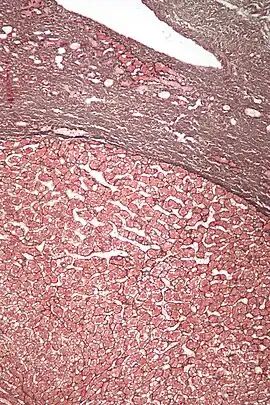

![]() Micrografía de un adenoma hepático (base de la imagen). Tinción hematoxilina-eosina | ||

Los adenomas hepáticos son, típicamente, nódulos bien circumscriptos que constan de hojas hepatocitarias con un citoplasma vacuolado de aspecto burbujeante. Los hepatocitos se disponen en un armazón de reticulina regular y más o menos igual a tres células de espesor.

El diagnóstico histológico de los adenomas hepáticos puede ser facilitado por la impregnación argéntica (tinción con sales de plata). En los adenomas hepáticos, el armazón de reticulina y los hepatocitos no forman capas de cuatro o más hepatocitos, como se ve en el carcinoma hepatocelular.

Las células parecen hepatocitos normales y son recorridos por vasos sanguíneos pero carecen de espacios porta y venas centrales.

Micrografía de adenoma hepático. Tinción hematoxilina-eosina.